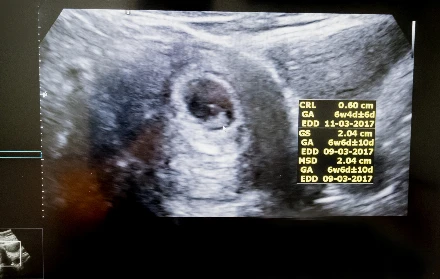

Az első szívhangok varázsa

A leendő baba szívének árulkodó dobbanása az egyik legizgalmasabb hang, amit a várandós szülők hallhatnak. Íme, minden, amit tudnod kell arról, hogyan növekszik a babádnak ez az alapvető rendszere.